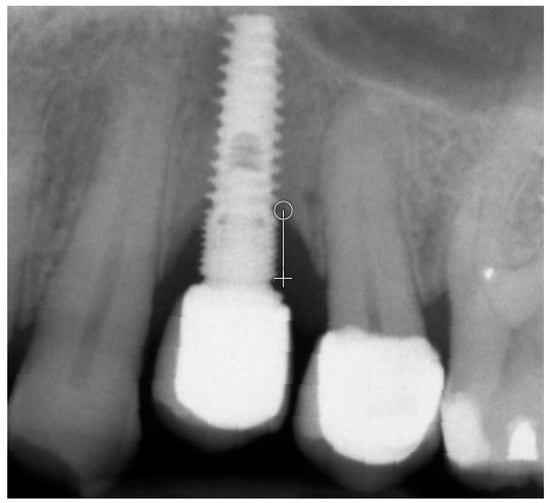

Figure 1.

Measuring of marginal bone loss on the radiographic images 5 years after the functional loading. White line indicates the implant platform to the bottom of the bone loss cavity.